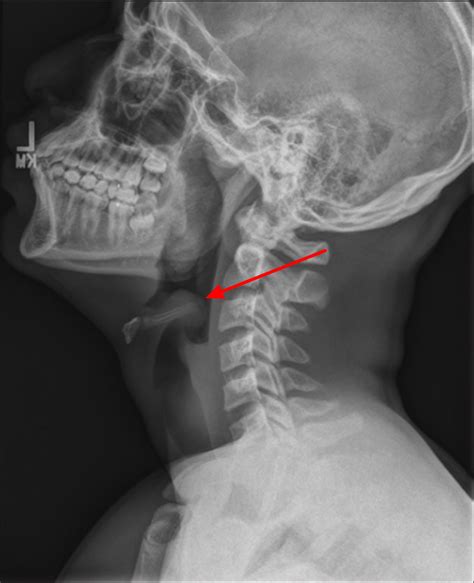

Thumb Sign Xray. Web steeple sign (also known as wine bottle sign and inverted v sign): Seen on ap radiographs of the neck or chest and neck demonstrates uniform narrowing of the subglottic airway distension of the hypopharynx is also seen due to the patient's attempt at decreasing airway resistance.

It is seen in midline sagittal projection as a projection of. Web the thumb lateral view is an orthogonal projection of ap/pa view. Indications as with all thumb radiographs, this is a view requested for a number of reasons including trauma, suspected inflammatory process or foreign body (to name a few). The thumb (first digit) reviewed under the thumb series. Web thumbprinting is a radiological sign of large bowel fold thickening, usually caused by edematous change, related to an infective or inflammatory process (colitis) or due to. Seen on ap radiographs of the neck or chest and neck demonstrates uniform narrowing of the subglottic airway distension of the hypopharynx is also seen due to the patient's attempt at decreasing airway resistance. The thumb, unlike other fingers, has only two phalanges: Other supportive measures include humidified oxygen.2. Web the thumb series for pediatrics often consist of a posteroanterior and lateral view only in order to minimize radiation dose to the patient. Web radiograph of the thumb.

Web the thumb series for pediatrics often consist of a posteroanterior and lateral view only in order to minimize radiation dose to the patient. Web the steeple sign (also called the wine bottle sign, and inverted v sign), refers to the tapering of the upper trachea on a frontal chest radiograph reminiscent of a. Xray thumb stock photos are available in a. As, thuma + l, signum the flexing of the terminal phalanx of the thumb against the flexed index finger, as in holding a piece of paper. Indications as with all thumb radiographs, this is a view requested for a number of reasons including trauma, suspected inflammatory process or foreign body (to name a few). The most important first step of. Web the thumb series for pediatrics often consist of a posteroanterior and lateral view only in order to minimize radiation dose to the patient. Seen on ap radiographs of the neck or chest and neck demonstrates uniform narrowing of the subglottic airway distension of the hypopharynx is also seen due to the patient's attempt at decreasing airway resistance. Other supportive measures include humidified oxygen.2. Web radiograph of the thumb. Web thumbprinting is a radiological sign of large bowel fold thickening, usually caused by edematous change, related to an infective or inflammatory process (colitis) or due to.